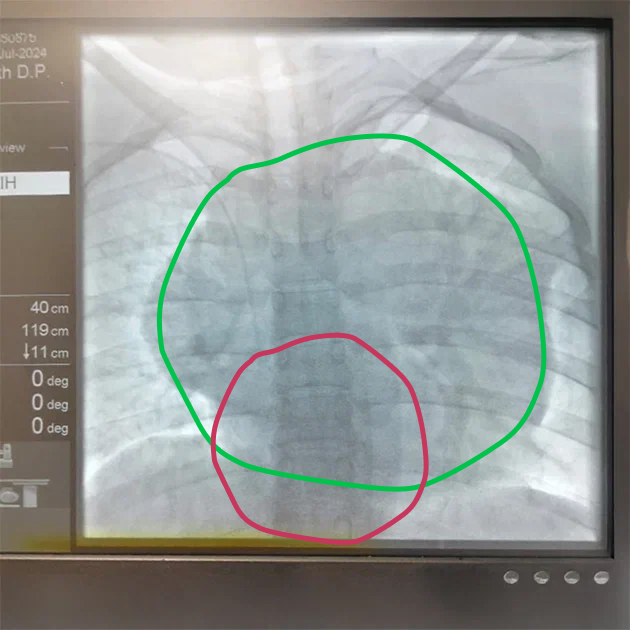

Отвезла другу-онкологу диск с визуализацией, и он подтвердил: огромная опухоль, 17 на 17 сантиметров. Даже не знаю, как я ее не замечала.

После двух курсов химии меня направили на обследование в Улан-Удэ — в моем городе его не проводят. Оно показало, что опухоль уменьшилась, но в сердце обнаружили тромб размером 3 на 5 см. Эту новость мне сообщили по телефону, когда я уехала за город погулять по дацану . Помню, как стояла на горе, смотрела на пейзажи, а голос в трубке перечислял все, что мне нельзя делать: казалось, даже дышать опасно.